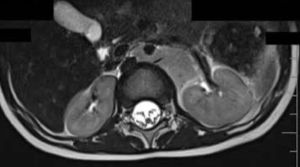

In this clinical quandary, investigators determine how to best treat patients with opsoclonus-myoclonus–associated neuroblastoma with bone marrow metastases.